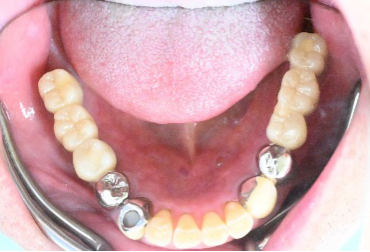

下の左右歯がないところに歯を入れたい。

治療内容

左右それぞれ3本歯がないところに2本ずつインプラントを埋入しました。

所感

上と下の歯の咬合接触がないすれ違い咬合です。上下義歯で対応するには最も難しいタイプの欠損状況です。治療開始前は、上下部分入れ歯が入っていましたが、入れ歯の安定が悪く、あちこちの歯茎に入れ歯が当たって痛く、満足に噛める状態ではありませんでした。上顎は、残ってる歯を活用するマグネット式総義歯を、下顎はインプラントを提案しました。上顎は、現在残っている歯の根管治療中です。上顎にマグネット式総義歯がはいれば、何でも食べられるようになります。

Before

▼初診時に使用していた部分入れ歯を装着したところ

▼インプラント埋入前

After

▼インプラント埋入後